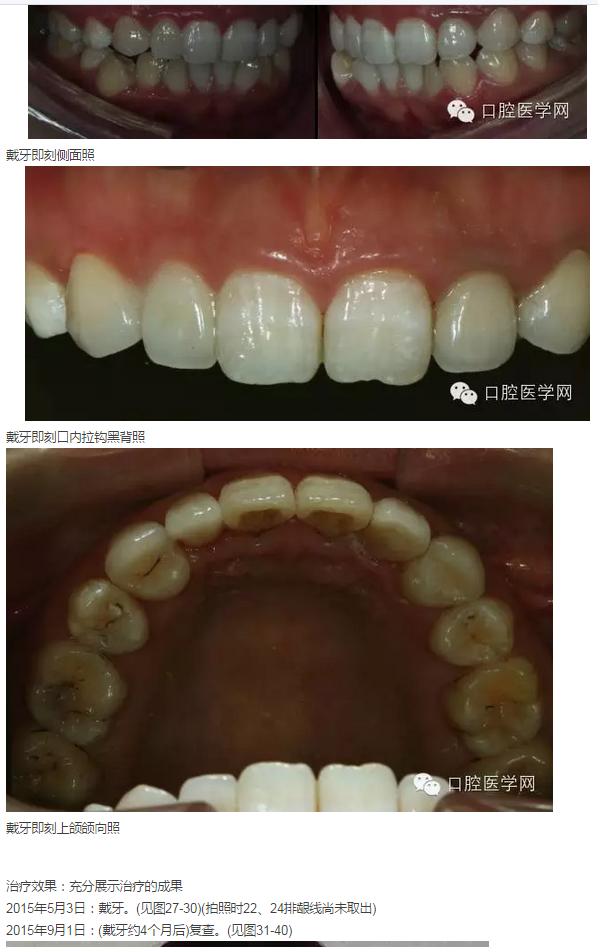

2015年5月3日:戴牙。(見圖24-30)(拍照時22、24排齦線尚未取出)